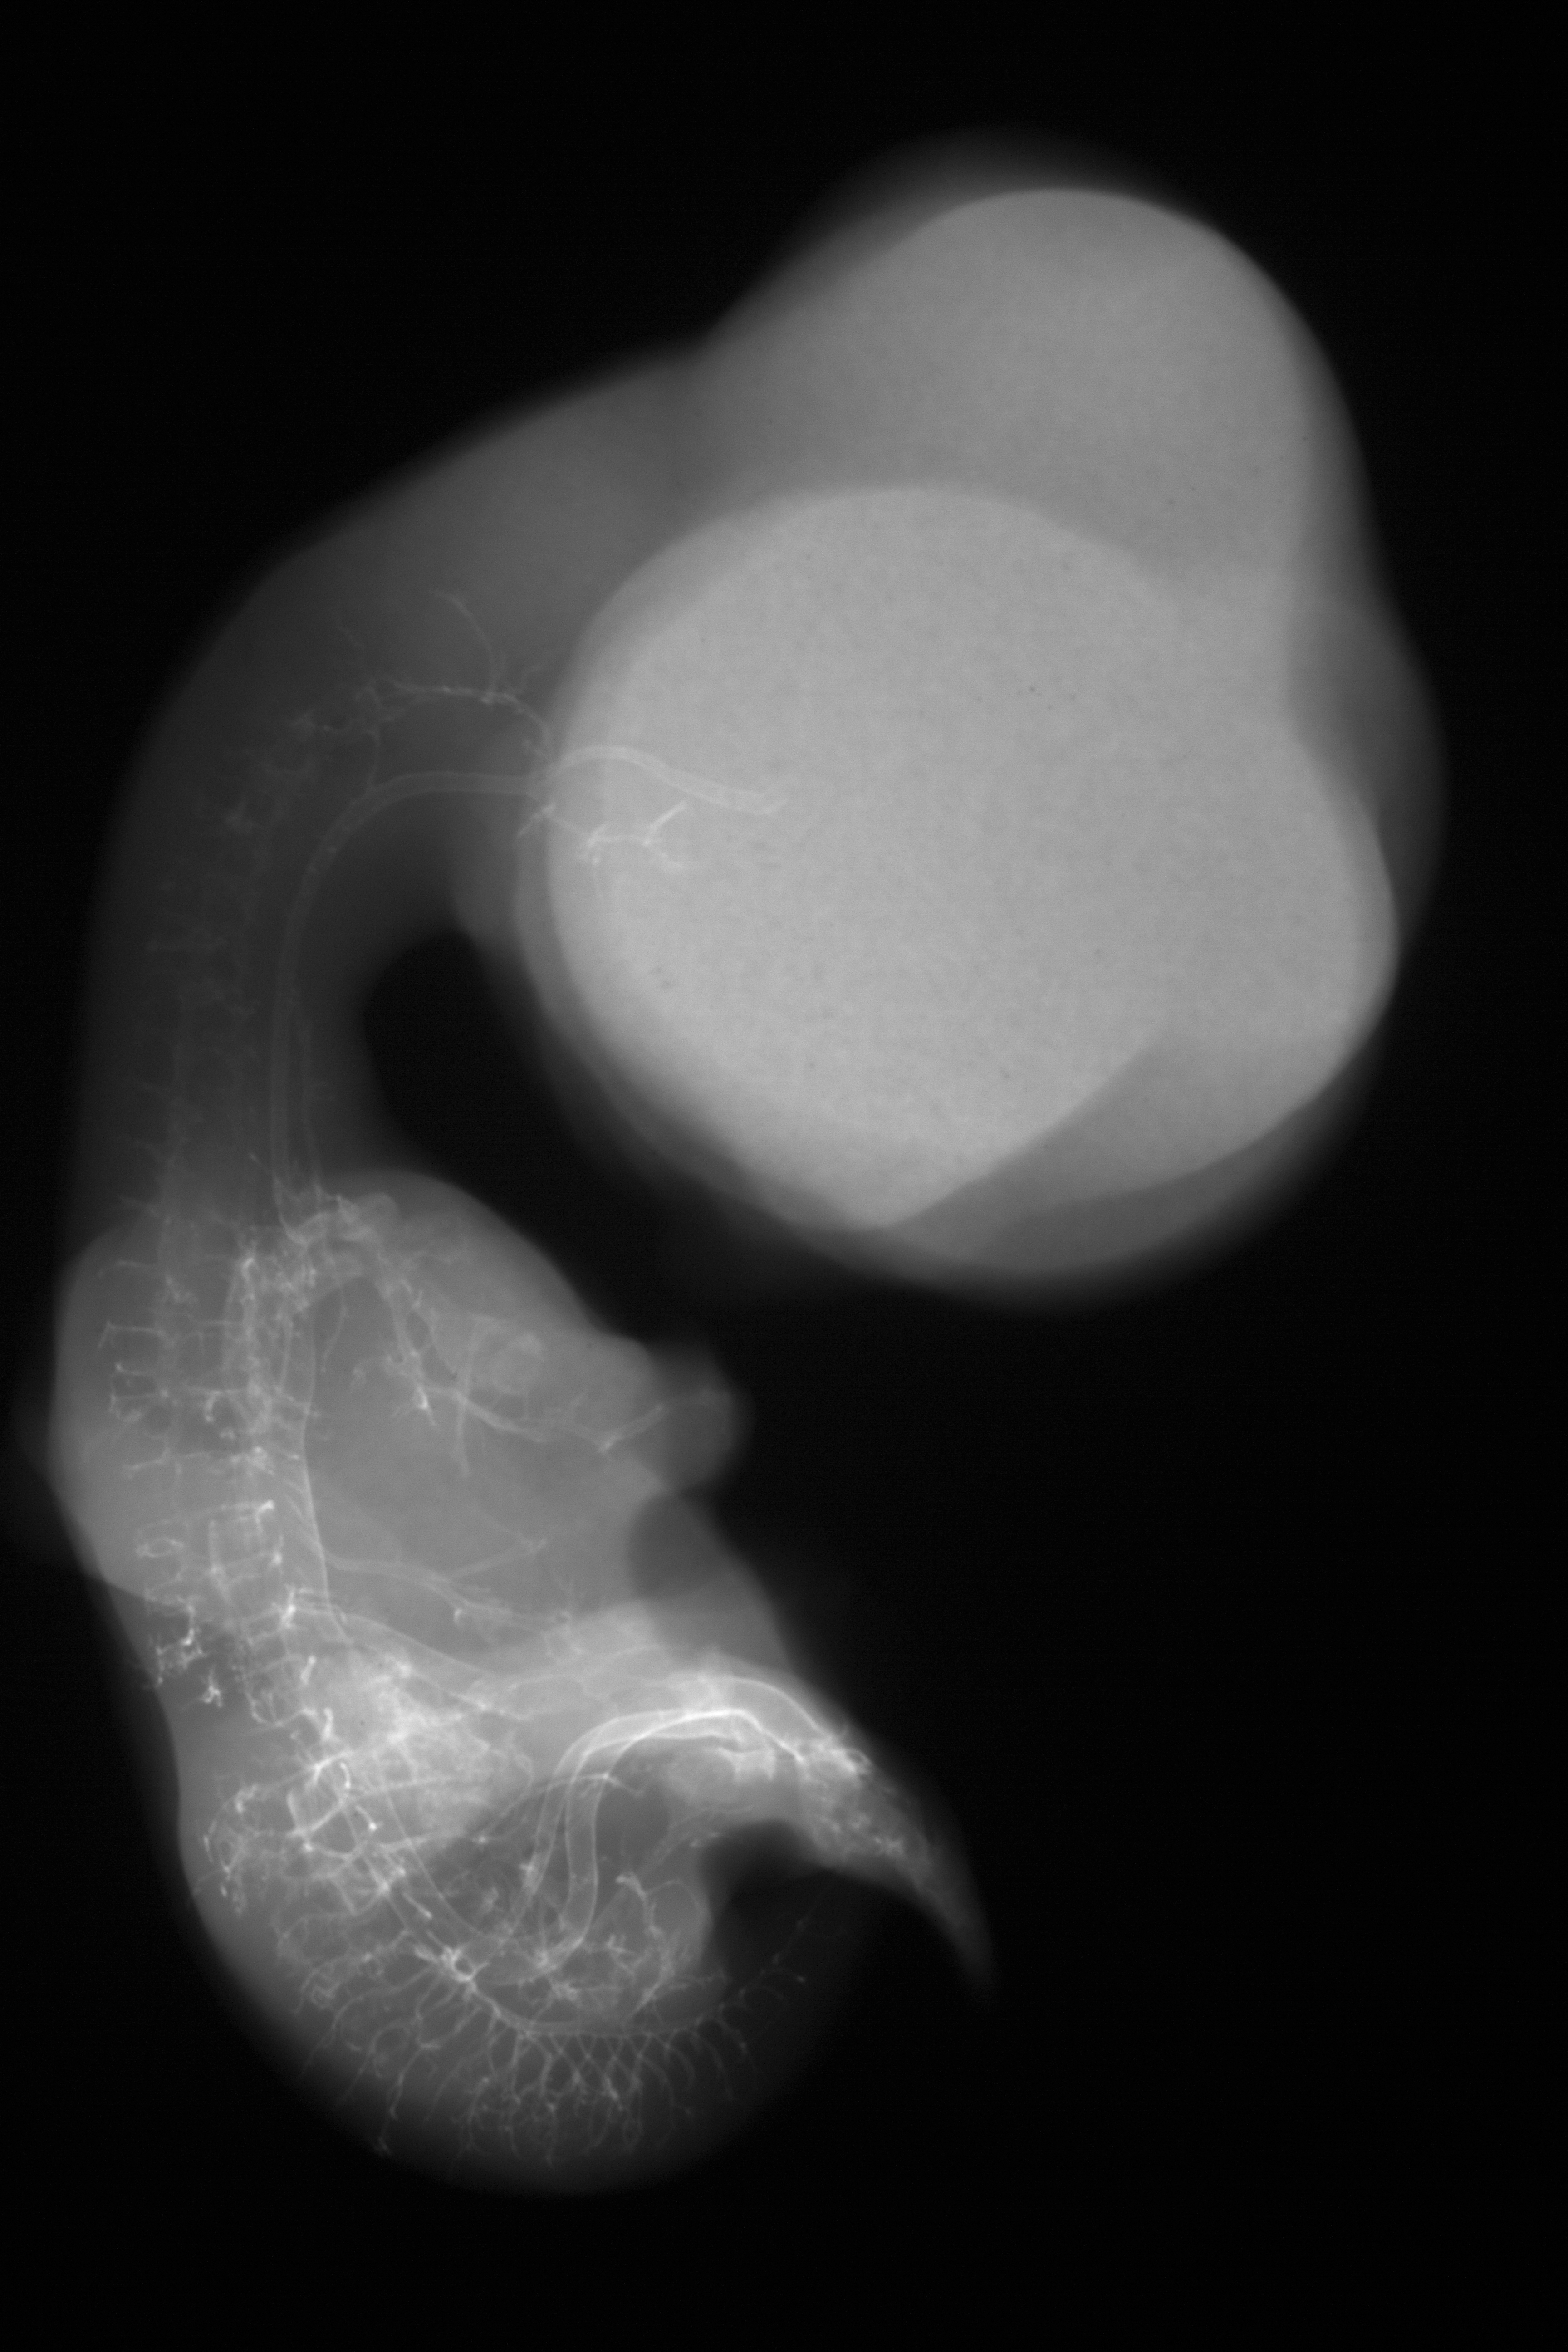

Chick Embryo Microangiography

Hamburger-Hamilton (HH) Stage 30 (approx. 6.5 days)

Stereo X-Ray Micrographs